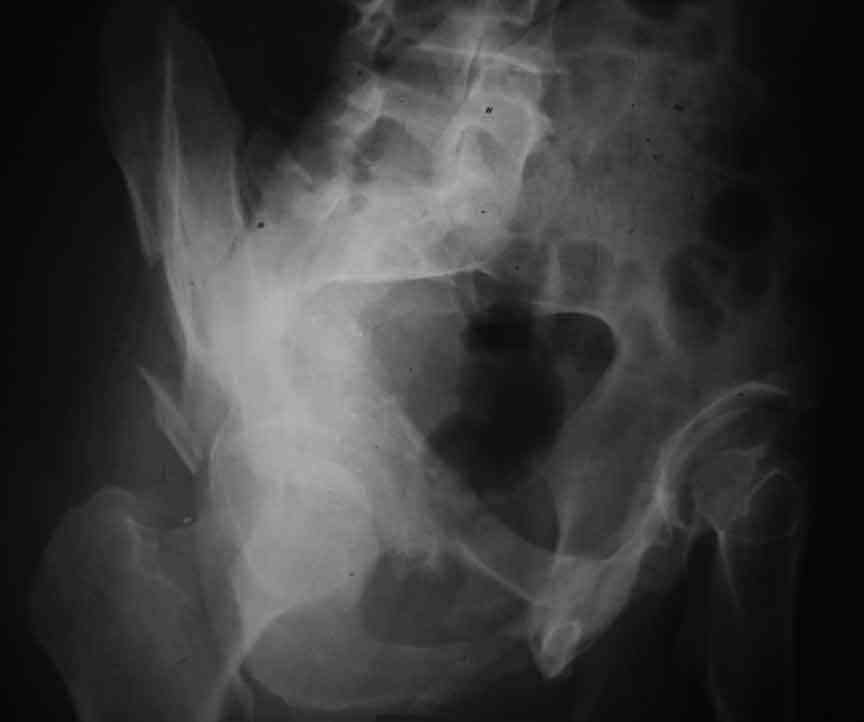

Dear Friends This is a 57 y old male.

Your input is welcome as to the classification of this fratcure, as well as the proposed management.

In my opinion it is a column fracture because the obturator foramen is interrupted. There is a fracture of the posterior wall. If we assume the ap view as an iliac view it could be an anterior comun fracture plus posterior wall. It is difficult also to judge the head of the femur.

From the x rays it appears like a bicolumnar fracture with iliac extension (AO C1).